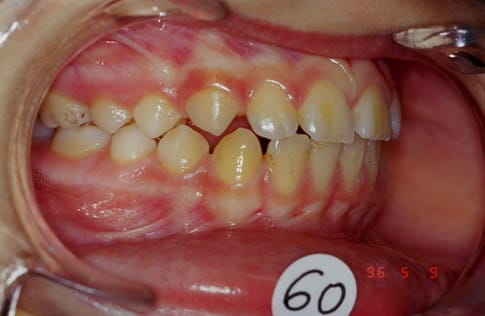

voici le 1er cas

Biproalveolie

1 a7nson - Eugenol

2 aijzeq - Eugenol

3 kwoluy - Eugenol

4 vduups - Eugenol

Cas n 1 suite

QH + Reeducation + Ecran buccal c'est tout